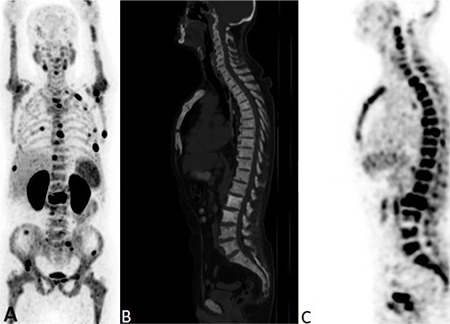

Objectives: To evaluate the relationships between volumetric 68Ga-prostate-specific membrane antigen (PSMA) positron emission tomography/computed tomography (PET/CT) parameters, Gleason score (GS), prostate-specific antigen (PSA) levels, histopathological data, and metastatic status in newly diagnosed prostate cancer (PCa) patients and to assess the predictive factors for progression despite treatment.

Methods: A total of 78 newly diagnosed patients with PCa who had 68Ga-PSMA PET/CT scans were included. Clinical parameters, histopathological data, and metastatic status were documented, and volumetric parameters of primary prostate lesions were measured. All obtained data were compared statistically.

Results: Primary prostate tumor maximum standardized uptake value (SUVmax) and GS were significantly related to serum PSA levels (p<0.05). PSA levels and SUVmax values were significantly higher in patients with lymph node metastases than in those without. GS was found to be significantly increased in metastatic patients. PSMA-derived tumor volume (PSMA-TV) and total lesion PSMA of the primary lesion had a significant relationship with PSA value, GS, and regional lymph node metastases. Receiver operating characteristic analysis, conducted in patients with metastatic and localized disease, identified the cutoff value for SUVmax as 10.85. According to the results of the logistic regression analysis, PSMA-TV was found to be a predictive factor for progression despite treatment.

Conclusion: 68Ga-PSMA PET/CT remains an invaluable imaging modality that should be considered first in PCa staging because of its superior compatibility with clinical and histopathologic data. The importance of this method goes beyond diagnostic accuracy; it also extends into the predictive domain, where the PSMA-TV value of primary prostate lesions is a potential predictor of treatment efficacy. This information is valuable for personalizing patient treatment, improving prognostic accuracy, and predicting clinical outcomes.